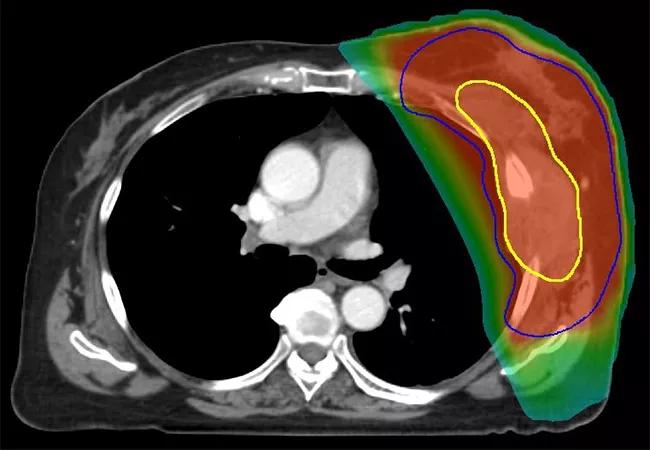

Following evaluation by a multidisciplinary team at Cleveland Clinic, the patient received neoadjuvant chemoradiation with 50 Gy in 25 fractions delivered once daily, with a 1-cm bolus applied to the chest wall for the first 13 fractions. Superficial hyperthermia was administered with a 915 MHz microwave applicator twice a week, separated by 72 hours, with a target temperature of 40°C 60 for 1 hour immediately prior to radiation. The patient also received gemcitabine concurrently at a dose of 500 mg/m2 weekly.

Five weeks after the patient completed chemoradiation, a contrast-enhanced computed tomography scan of the chest showed no significant change in the size of the primary mass. Expected post-radiation changes, including asymptomatic radiation pneumonitis and a small pleural effusion, were visible. Given the lack of evidence of distant metastasis, surgical resection was performed 2 weeks later. Because the patient’s disease was locally advanced, the procedure included resection of the chest wall, portions of ribs 3 to 8, and a wedge resection of the lung lingula. Titanium mesh measuring 20 x 20 cm was used for reconstruction of the 18-cm postoperative defect; prolene mesh was used to repair a small residual defect. Following wound closure, a Cleveland Clinic plastic surgery team used a latissimus dorsi myocutaneous flap, pectoralis minor flap advancement, pectoralis major muscle flap advancement, and serratus muscle flap advancement to perform the multisite reconstruction.